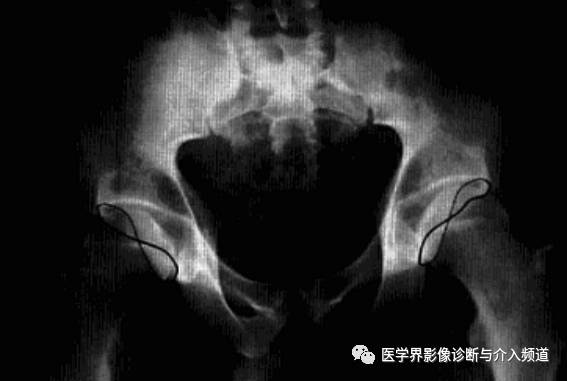

血友病性髋关节炎

血友病患者关节内反复出血所致关节退行性病变,好发于活动多和承受重力的关节,最常累及膝、肘、踝关节,髋关节较少。

病理:关节内出血刺激滑膜炎症反应、增生、绒毛形成,关节囊及滑膜增厚、纤维化,软骨下出血可致软骨坏死脱落,骨质增生、囊变,关节畸形或纤维强直,儿童骨骺增大、骺板提前闭合。

临床表现:男性,儿童多见,关节肿胀,肌肉萎缩,多脏器出血症状,实验室凝血异常。

影像诊断:X线平片典型改变可确诊,CT及MRI可清晰显示软骨及腔内改变。1、平片:早期髋关节间隙增宽,关节囊肿胀,软组织密度增高,骨性关节面光整。中后期出现骨侵蚀,关节间隙狭窄或消失,软骨下骨板致密,边缘骨赘形成及囊变,儿童骨骺增大、骺板提前闭合。

2、CT:髋关节腔内高密度或钙化,关节囊增厚,软骨下骨质小圆形和不规则软组织密度区,伴周围硬化缘,正常骨纹理消失,骨端骨质疏松。长期者呈骨性关节炎改变。

3、MRI:髋关节腔内出血为特征表现,滑膜及关节囊明显增厚,增强有明显强化;晚期关节面下硬化性病灶,骨质囊变,软骨坏死,纤维组织增生,陈旧性出血改变。